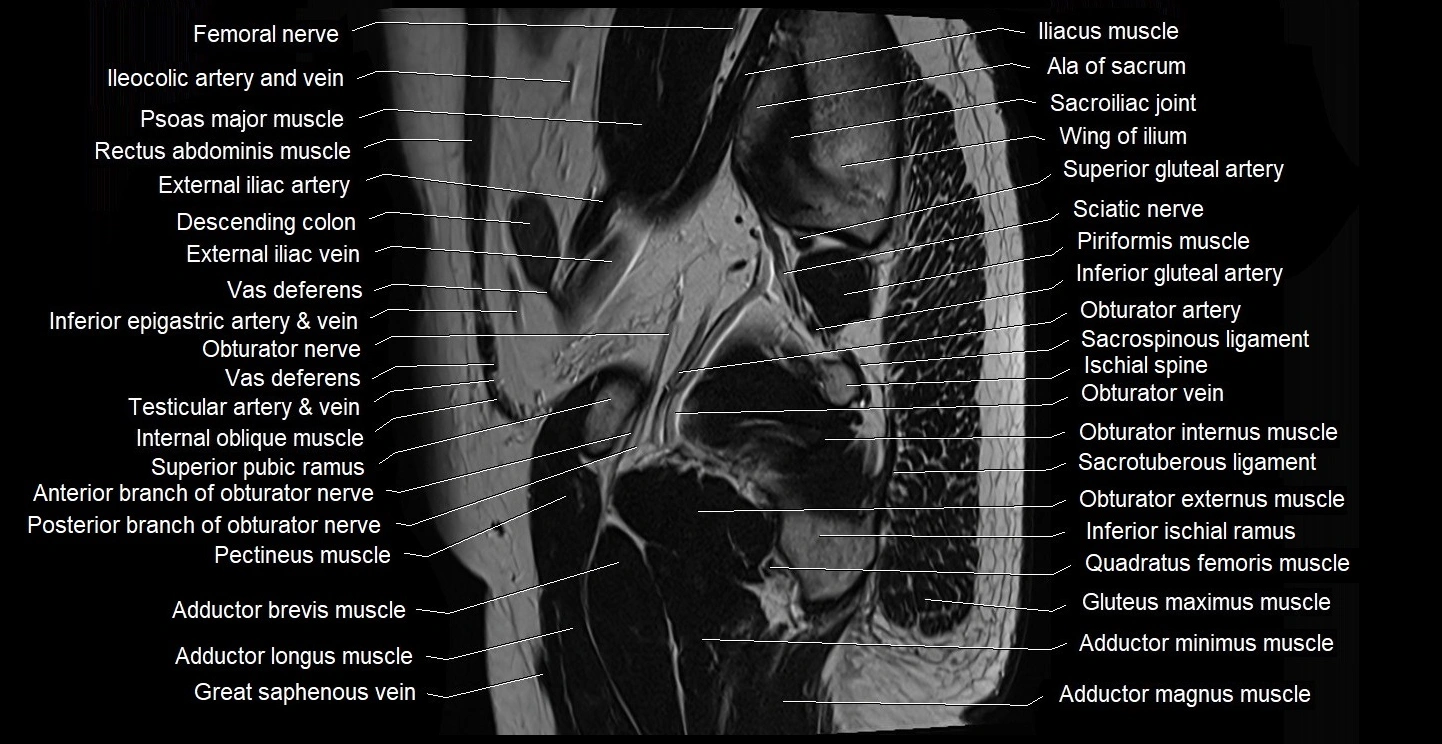

- Adductor brevis muscle

- Adductor longus muscle

- Adductor magnus muscle

- Adductor minimus muscle

- Anterior division of obturator nerve (Anterior branch of obturator nerve)

- External iliac artery

- External iliac vein

- Femoral nerve

- Gluteus maximus muscle

- Iliopsoas muscle

- Iliopsoas tendon

- Iliopubic eminence

- Inferior epigastric artery

- Inferior epigastric veins

- Inferior pubic ramus

- Internal oblique muscle

- Obturator artery

- Obturator externus muscle

- Obturator internus muscle

- Obturator nerve

- Obturator vein

- Pectineus muscle

- Piriformis muscle

- Posterior division of obturator nerve (Posterior branch of obturator nerve)

- Psoas major muscle

- Sacroiliac joint

- Sacrospinous ligament

- Sacrotuberous ligament

- Sartorius muscle

- Sciatic nerve

- Superior gluteal artery

- Superior pubic ramus

- Vas deferens

- great saphenous vein